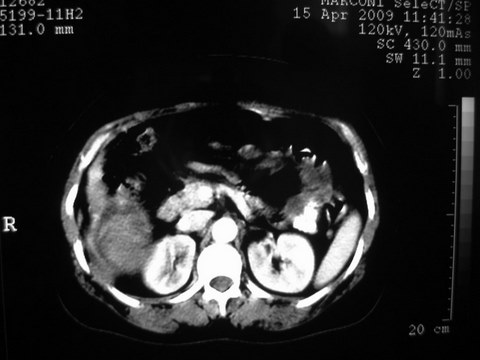

患者 女 51岁 两天前感觉上腹疼,无明显诱因,b超示肝右叶囊实性占位,边缘清楚,其内回声不均匀,ct增强如图,大家看看是什么 ,病人一年前及两月前b超检查只是提示胆囊炎

外院术后,证实肝癌合并出血

特点:1,病灶发展迅速,(2月前正常)[br] 2,囊实性,且并边界清晰光滑,呈右后叶赘生性。囊性区无强化,实性部分较多轻度强化,边界欠清。考虑囊腺癌或囊腺瘤。

增强扫描好像都没有强化的,不管灶周还是灶中心,支持考虑包虫病,别不除外肝囊内内出血,那些一块一块的为血凝块

出病理 中分化肝细胞癌合并出血